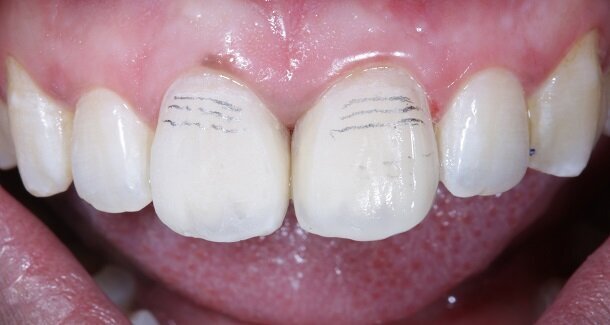

Fig 13 and 14 -Transitional Line angles were marked using a pencil and made prominent using medium grit 3M Soflex Discs proximally. The apparent faces of both the teeth were thus, created.

Fig 15 and 16 - For the surface texture; vertical surface macro-anatomy showing developmental grooves (mesial and distal) were marked using a pencil and created using the red ring finishing bur.

Fig 17- Horizontal surface micro-anatomy, that is, the Perikymata or imbrication lines were marked cervically and incisally, using a pencil and created using the red ring finishing bur.

Line angles can be used to create illusions of the tooth being wider or narrower as needed, especially in diastema closures. For better control, finishing burs can be used in the contra-angled handpiece with the help of a convertor.